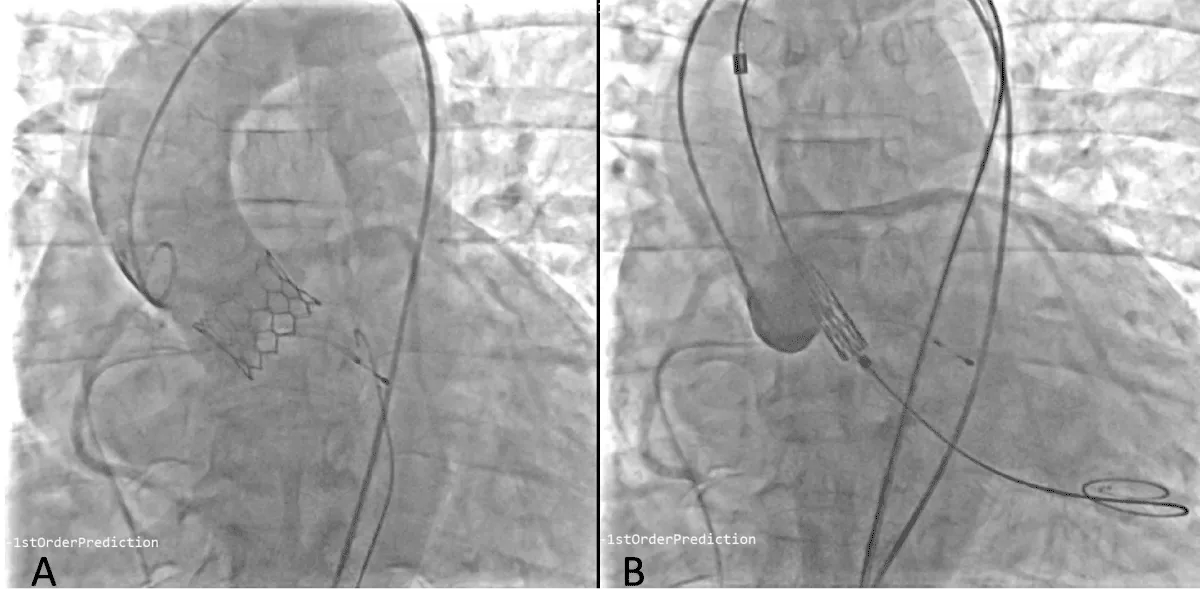

After obtaining consent, access was obtained through the right femoral vein and artery. Under 4D Transesophageal Echocardiography (4D TEE) guidance, the first transseptal puncture was performed with a broken Brough needle, and the LA wire was inserted through femoral venous access (Figure 1). Right femoral artery access was used for retrograde crossing of the aortic valve (AV) (Figure 2), and a Teflon wire was placed in the left ventricle. The aortic valve (AV) was dilated with a 14 mm ATLAS GOLD (BARD) balloon (Figure 3, Video 1).

Download Image

Figure 2: 4Dimensional multiplanar transoesophageal echocardiography view of aortic valve.

Figure 3: Fluoroscopic image of aortic valve. Balloon dilatation of aortic valve under fluoroscopy and transoesophageal echocardiography (Red arrow), yellow arrow – Left atrial wire, white arrow- Right ventricular pacing lead, black arrow- Balloon across the aortic valve.

Following a single dilatation, the AV gradient decreased from 82 mm Hg to 30 mm Hg without aortic regurgitation (AR). Subsequently, the mitral valve (MV) was dilated with a 26 mm Inoue balloon (Figures 4,5) (Video 2). After a single dilatation, the MV gradient was reduced from 35/21 mm Hg to 12/5 mm Hg, and the MV area increased from 0.5 cm2 to 1.6 cm2 (Figure 6)